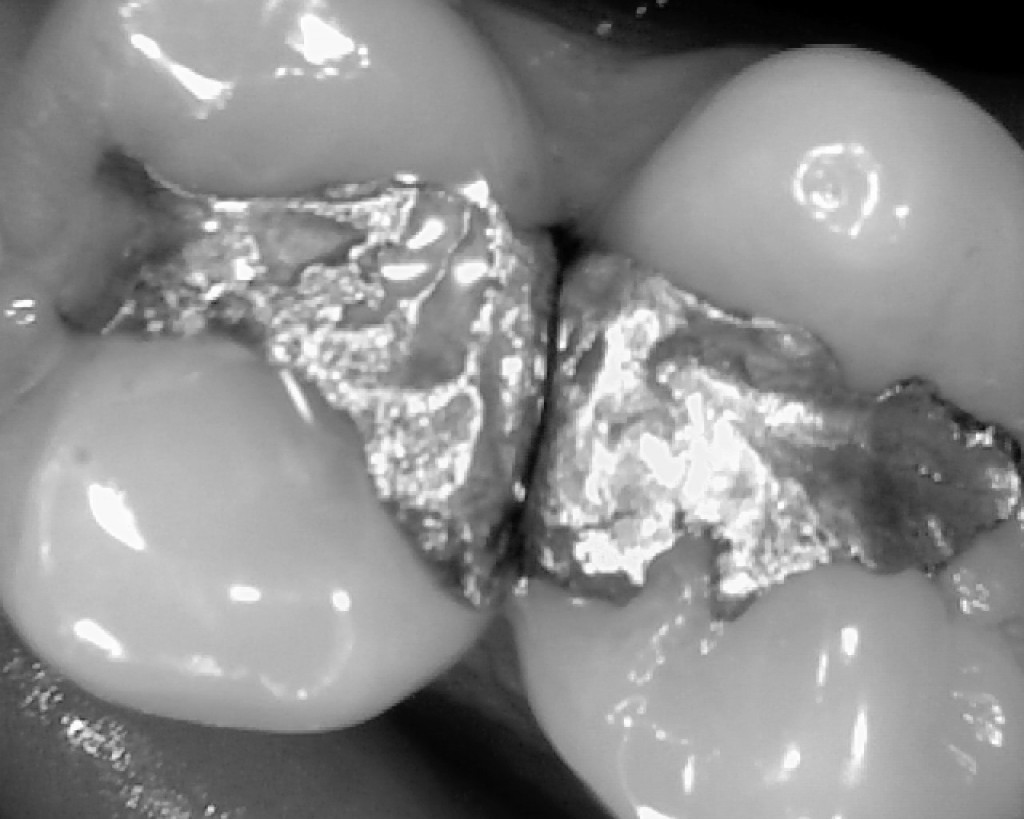

Silver amalgam fillings consist of between 48 and 52% inorganic mercury and 20% silver, with the remainder a mix of copper, tin and zinc.  Some people may be particularly sensitive to any of these elements, including those that are necessary for proper cellular functioning, but of all these mercury is the most highly toxic.

Many people are exposed to mercury from other sources than metal fillings, including fish consumption and occupational sources.  When it comes to fillings, there is a significant difference in exposure depending the on the surface area of the filling.  Large fillings, as one might expect, will result in higher levels of exposure than smaller fillings.  As mercury tends to accumulate, the length of time the filling is in place, while it may not matter in terms of daily exposure, is significant in terms of how much mercury is built up in the organs and tissues.

Pregnant women are warned to avoid eating certain types of fish due to the concentrations of mercury they often contain, and mercury thermometers are obsolete and nearly impossible to find.  But silver amalgam, an alloy consisting of half mercury and half a mix of silver, copper and tin, are commonly used to fill dental cavities.

Some scientists believe that amalgam fillings can leak mercury, which is inhaled and absorbed by the lungs, as well as swallowed and absorbed by the stomach and intestines.  Dr. Kimberly Baer, a dentist practicing in Maryland, explains that mercury fillings may cause few problems in healthy people, but small children, pregnant women, and individuals with weakened immune systems may not be able to effectively excrete the neurotoxin.  For these individuals, mercury can accumulate in the tissue and cause mercury poisoning.

Many people with amalgam fillings opt to have them removed after discovering that they contain mercury.  Most of them are never actually diagnosed with mercury poisoning, but may still notice increased energy levels and relief from a variety of health issues.

The American Dental Association does not recommend removing fillings that are not causing significant problems due to the potential for further weakening the tooth in the process and due to the potential for increased exposure from the procedure.